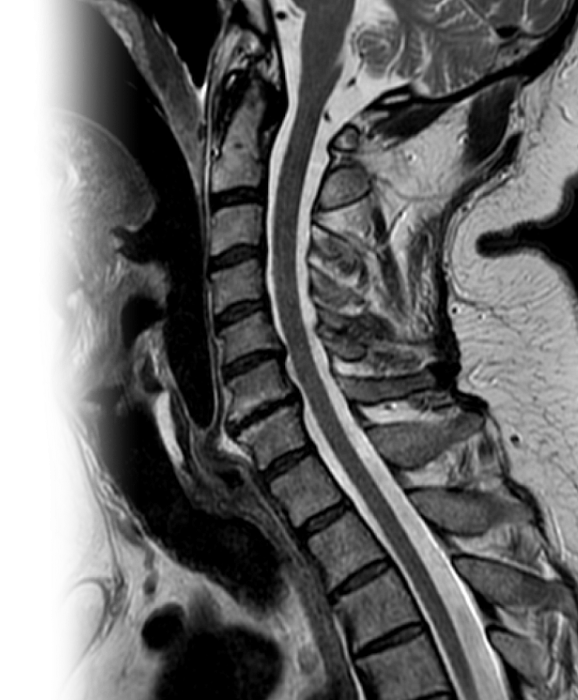

МРТ нескольких отделов позвоночника МРТ нескольких отделов позвоночника

МРТ нескольких отделов позвоночника

Магнитно-резонансная томография нескольких отделов позвоночника – важный метод исследования, который позволяет оценить состояние двух или трех отделов позвоночника.